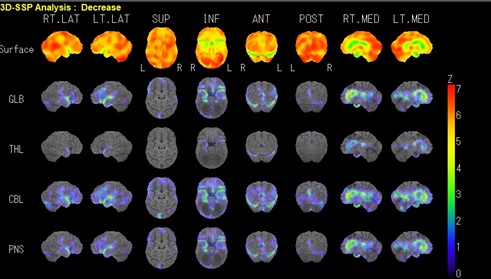

当院では、シーメンス社製 SPECT装置を使用しています。SPECT(スペクト)とは、Single Photon Emission CTの略で体の周りをカメラがゆっくり回転しながら、事前に投与した放射性医薬品から出るガンマ線を検出する撮像方法です。撮影した画像は任意の断面で画像化することやカラーマップで血流の評価を行う事ができます。

脳の血流状態や働きを見る検査です。脳血管のわずかな変化を見つけることができ、早期の脳血管障害や脳の機能評価に利用されます。この検査で脳梗塞などの脳血管障害、認知症などの診断、評価、治療効果判定に役立ちます。